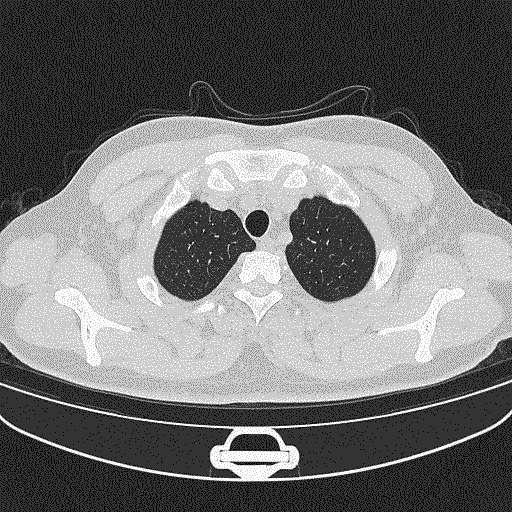

入本院前2周时CT.gif